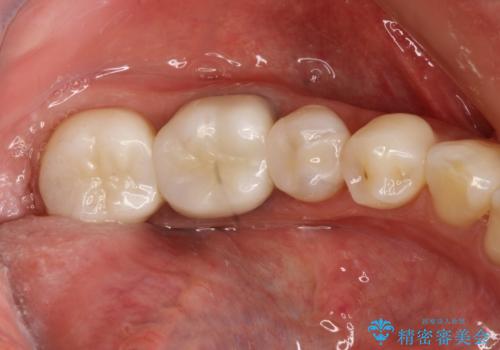

奥歯のむし歯を治したい セラミッククラウンによる補綴治療

大きい虫歯 根管治療〜オールセラミッククラウン